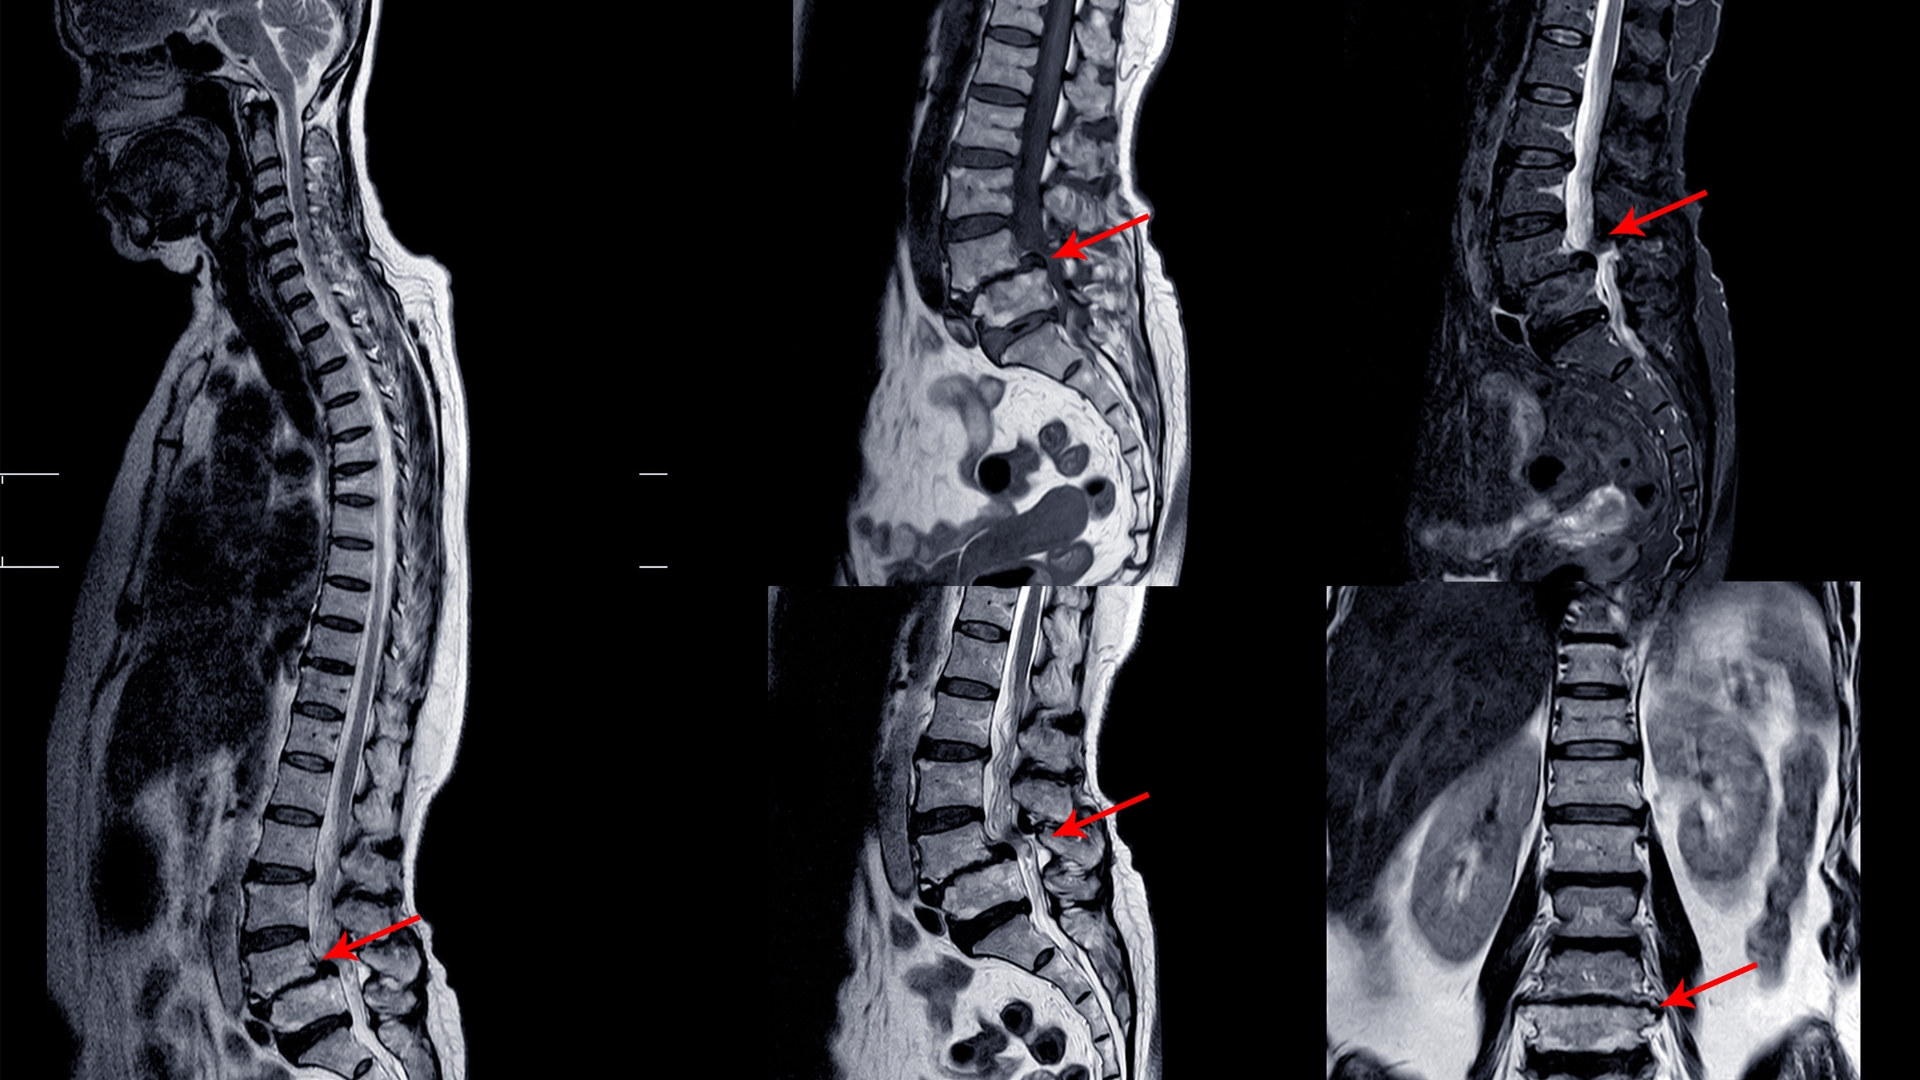

Pivd, also known as a Prolapsed Intervertebral Disc, is a condition where the soft cushion-like disc between the vertebrae of the spine slips out of place, potentially causing pain, numbness, and weakness in the affected area. Treatment for Pivd often involves a combination of physiotherapy techniques such as manual therapy, exercise therapy, and pain management strategies to reduce symptoms, improve mobility, and promote healing.

Disc prolapse, also known as a herniated disc, occurs when the soft cushion-like disc between the vertebrae of the spine bulges or ruptures, causing potential nerve compression and resulting in pain, numbness, or weakness in the affected area. Treatment for disc prolapse often involves a combination of physiotherapy interventions, including manual therapy, therapeutic exercises, and pain management techniques, to alleviate symptoms.

Cervical and lumbar spondylitis physiotherapy utilizes a combination of exercises, manual therapy techniques, and modalities to alleviate pain, improve spinal mobility, and strengthen supporting muscles. Through targeted interventions, physiotherapy aims to reduce inflammation, improve posture, and enhance the function of the cervical and lumbar spine, leading to increased comfort and improved quality of life.

Sciatica pain treatment aims to alleviate the pain and discomfort caused by compression or irritation of the sciatic nerve. It typically involves pain management, physical therapy exercises, heat/cold therapy, and postural corrections. In some cases, manual therapy techniques or steroid injections may be used, while surgery is considered only in rare instances. Seeking professional guidance ensures an appropriate and personalized treatment plan for effective relief and improved function.